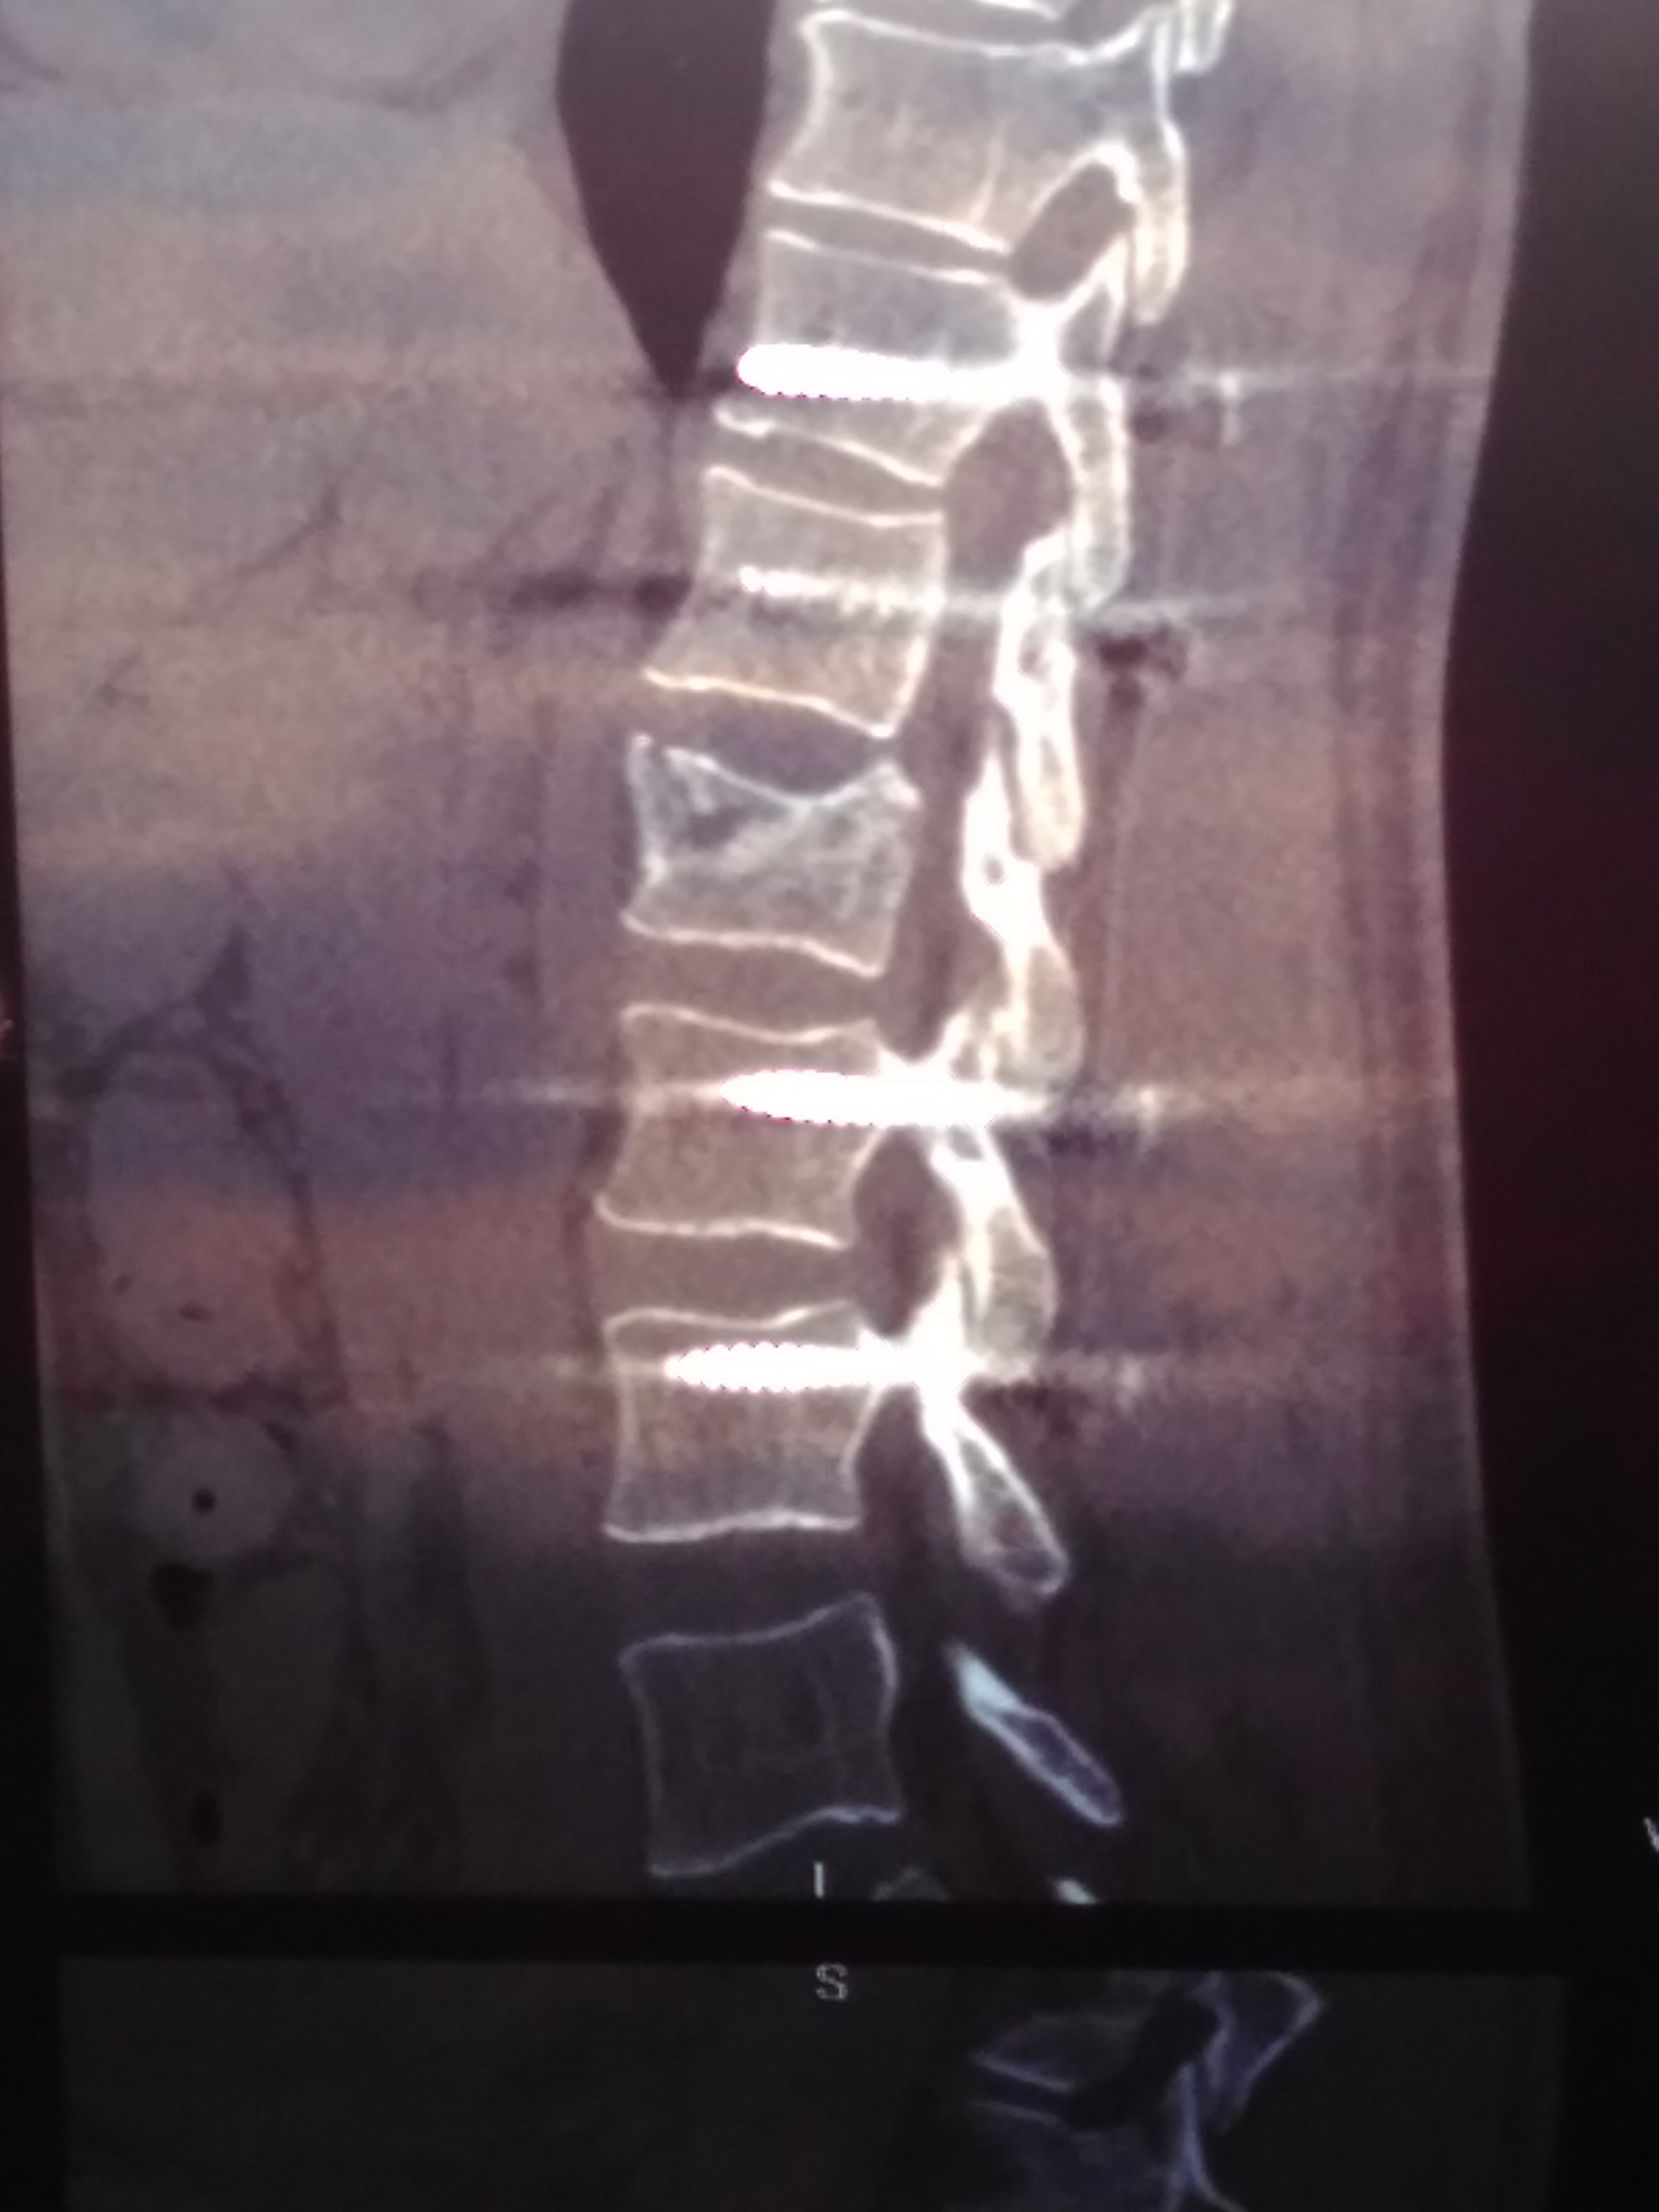

20 мая в результате падения с высоты получил взрывной перелом L1 типа В3, полное вертикальное и горизонтальное расщепление со смещением отломков задне-верхнего угла до 3,5 мм и переднего до 4,5 мм. А также вертикальный перелом Th12 типа В2 без смещения и расщепления. Через 5 дней была проведена операция ТПФ Th11,12-L2,3

7 августа (через 2,5 месяца) была сделана повторное КТ (снимки которого прикладываю). Со слов оперирующего доктора позвонок L1 не срастается, мелкие осколки "растворились", требуется операции по замене L1. В описании написано: частичный остеолиз краев фрагментов, с наличием диастазов до 5-6 мм.

12.jpg

11.jpg

01.jpg